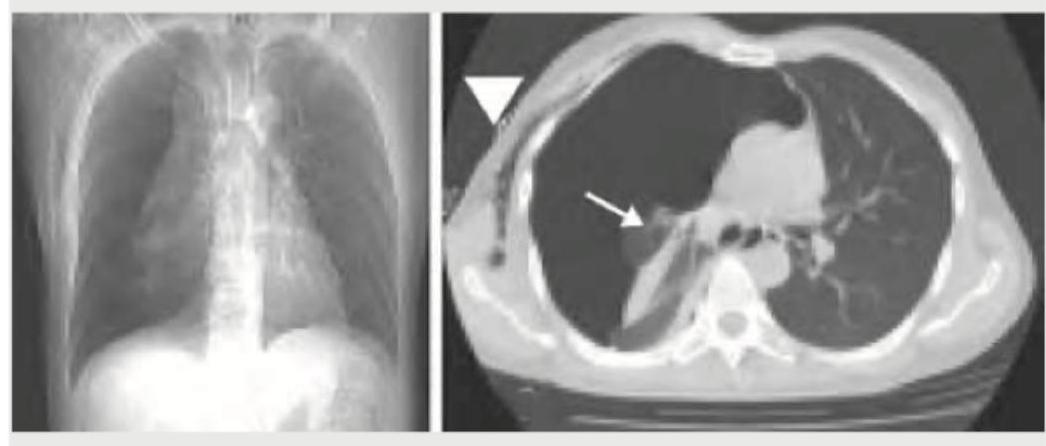

Question 9: An 18-year-old boy is brought to the hospital with difficulty in breathing after a bar fight. What does the given CT chest show?

- A. Pneumothorax (Correct Answer)

Explanation: ***Pneumothorax*** - The CT image shows a clear **absence of lung parenchyma** extending to the chest wall, with a visible **visceral pleural line** separated from the parietal pleura. This indicates air in the pleural space, which is characteristic of a pneumothorax. - The patient presenting with **difficulty in breathing** after a bar fight (implying trauma) is consistent with a **traumatic pneumothorax**. *Consolidation* - **Consolidation** appears as a region of increased attenuation (whitening) on CT, usually with **air bronchograms**, indicating filling of alveolar spaces, which is not seen here. - While it can cause difficulty breathing, it results from infection or inflammation, not typically direct trauma creating an empty space like in the image. *Pulmonary contusion* - **Pulmonary contusion** would appear as areas of **ground-glass opacity** or **consolidation** within the lung parenchyma due to bleeding and edema, without a significant collapse of the lung. - The image distinctly shows a collapsed lung with a clear air-filled pleural space, not parenchymal injury. *Haemothorax* - A **hemothorax** would show a **fluid collection** (appearing white or grey) in the pleural space, often layering dependently, which is not the primary finding on this image where an air-filled space is prominent. - While a traumatic event could lead to both pneumothorax and hemothorax (**hemopneumothorax**), the most striking feature evident here is the air within the pleural cavity causing lung collapse.